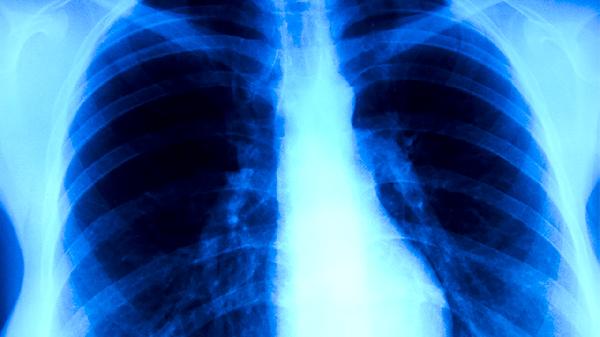

胸部X线可显示肺结核的典型病变特征,如肺上叶浸润影、空洞形成或纤维钙化灶。该检查发现异常阴影时,需与肺炎、肺癌等疾病鉴别。活动性肺结核常表现为边缘模糊的斑片状阴影,陈旧性结核则多见边界清晰的纤维条索影。检查无须特殊准备,但孕妇应告知医生,必要时采取防护措施。